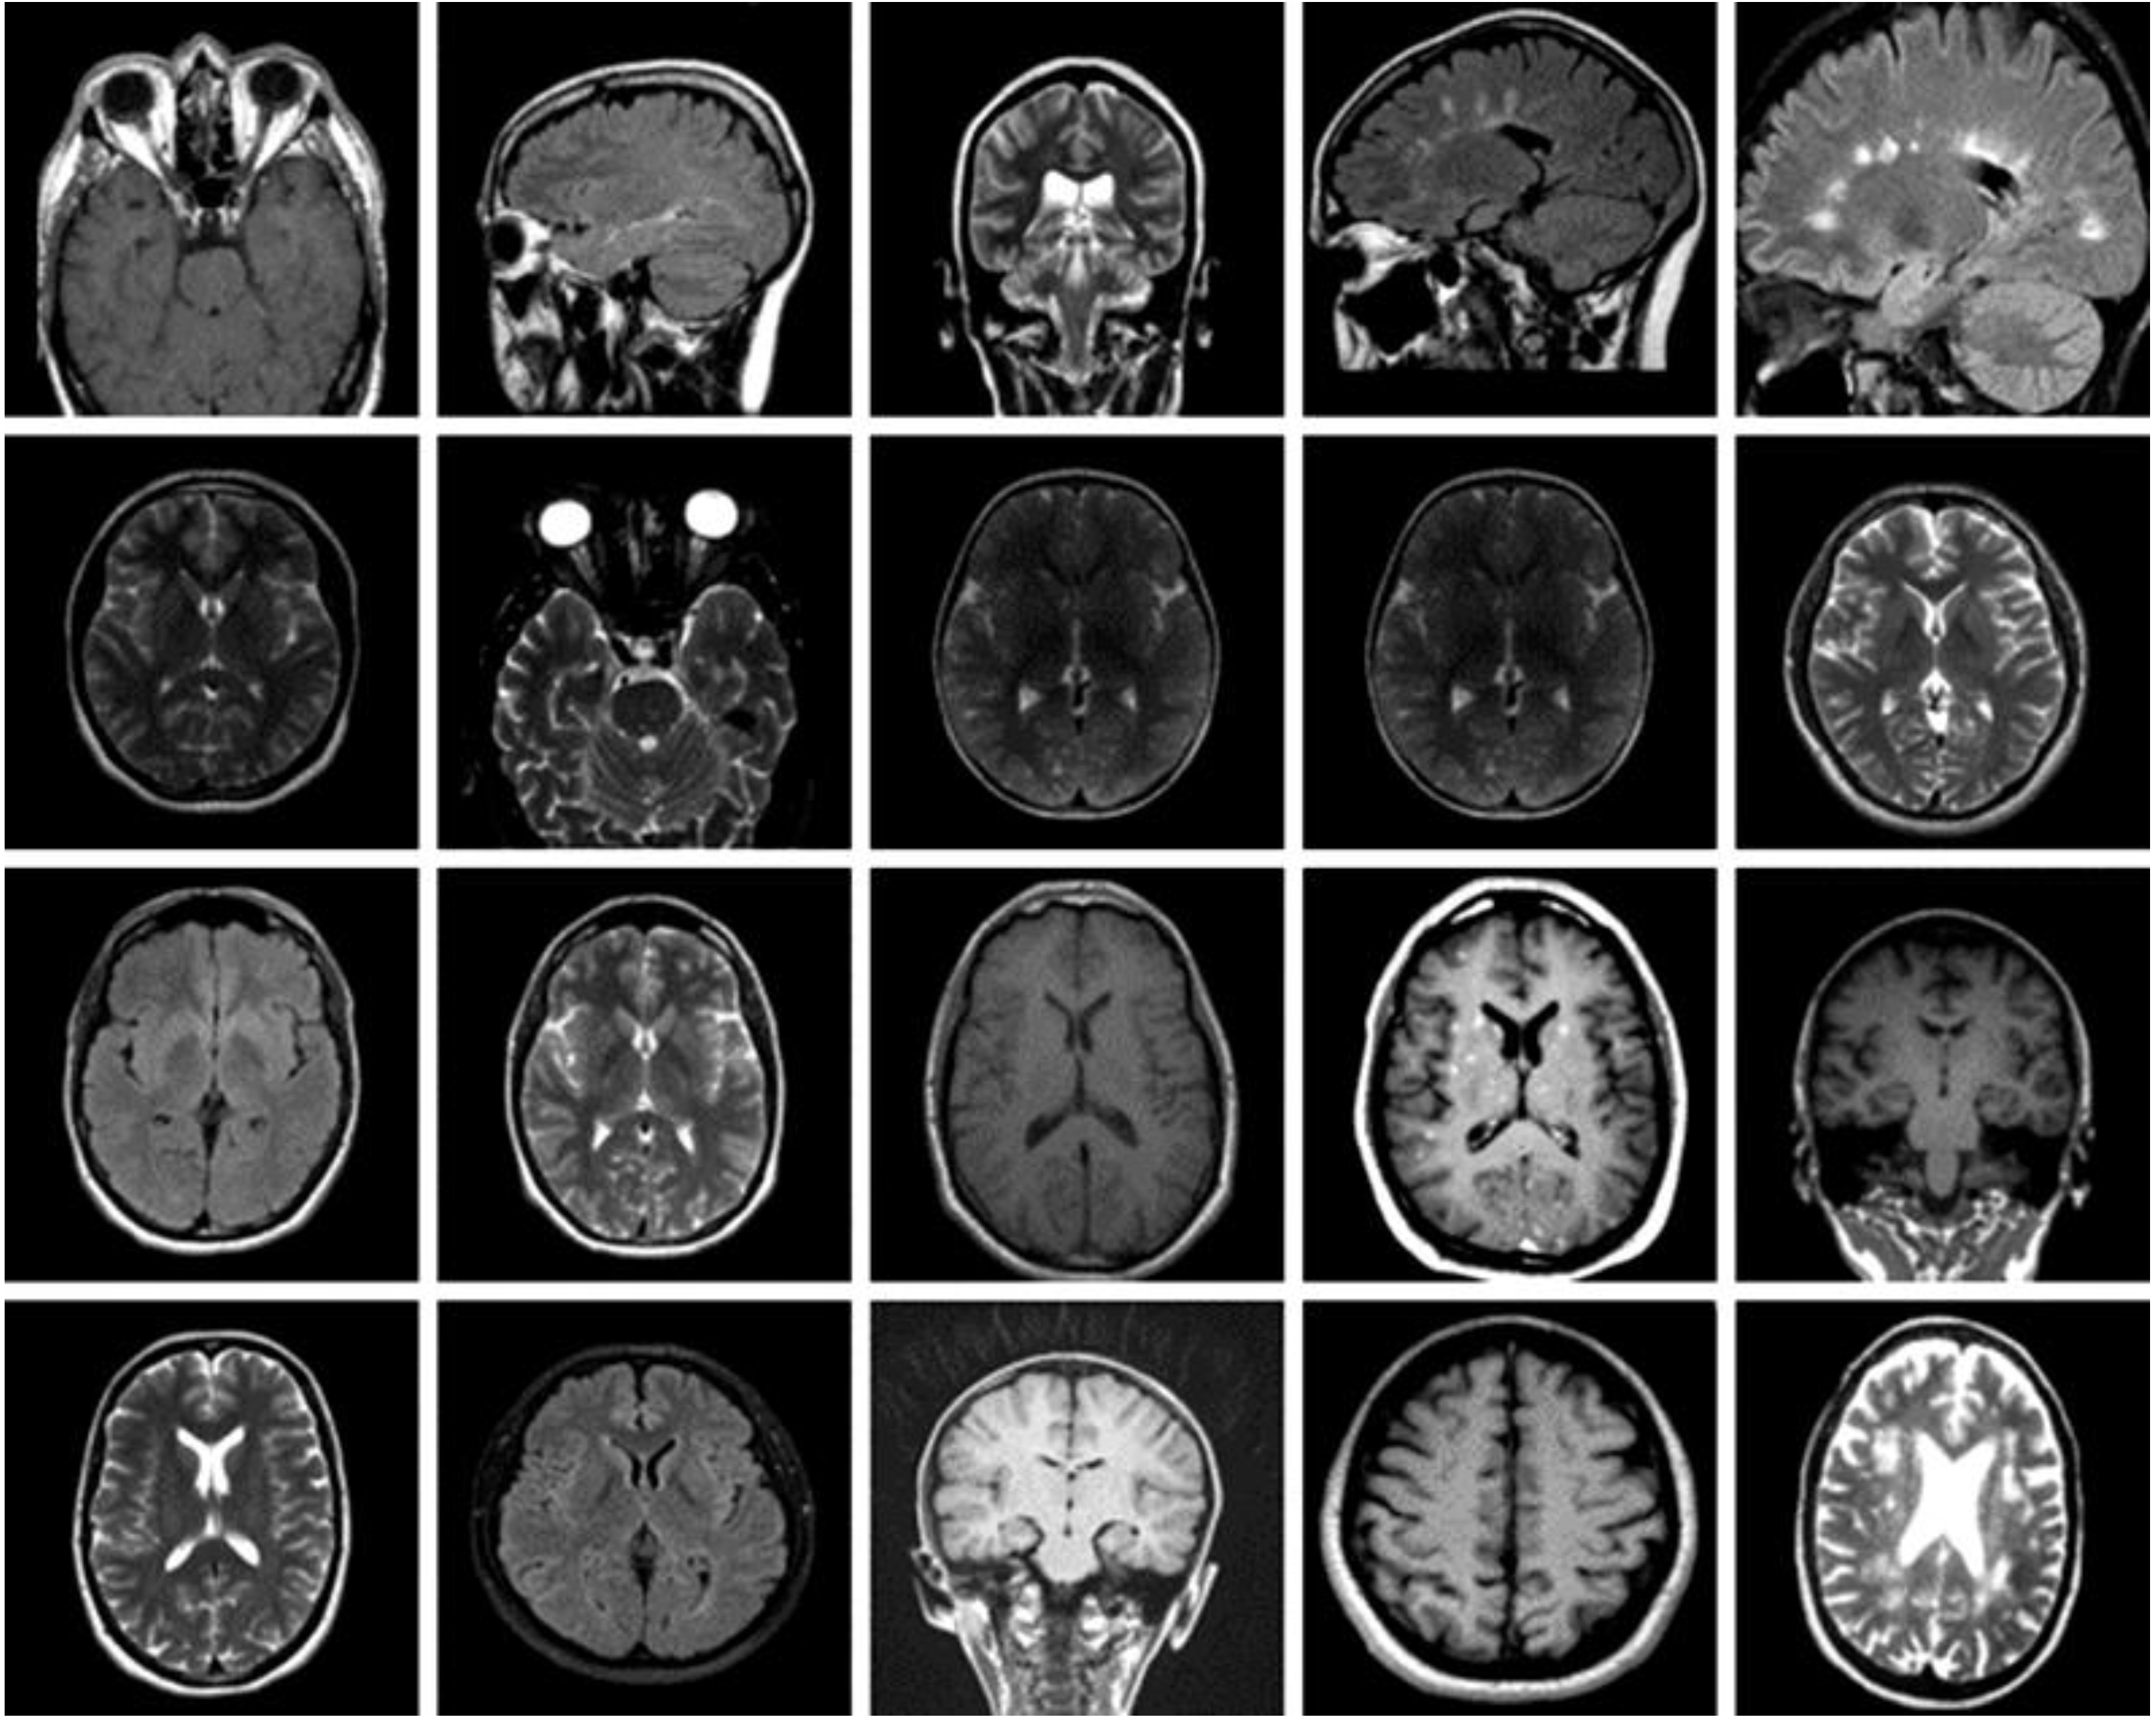

The dataset used for this current work is compiled from three other datasets: Figshare, SARTAJ, and Br35h. This composite dataset contains 2880 T1- weighted contrast-enhanced MRI brain images [26]. Gadolinium was used as contrast agent in these images. The target dataset has 829 images for glioma tumor, 825 images for meningioma tumor, 830 images for pituitary tumor and 396 images for no tumor cases. The images of the target dataset have a resolution of 512 × 512 × 3 with 24 bits color depth. Figure 1, Figure 2, Figure 3 and Figure 4 show some examples for each possible class: no tumor, glioma, meningioma, and pituitary tumor, respectively. The target dataset is split with 70% used for training and the remaining 30% kept aside for estimating the validation accuracy.

Figure 1.

Examples of MRI scans with no tumor.